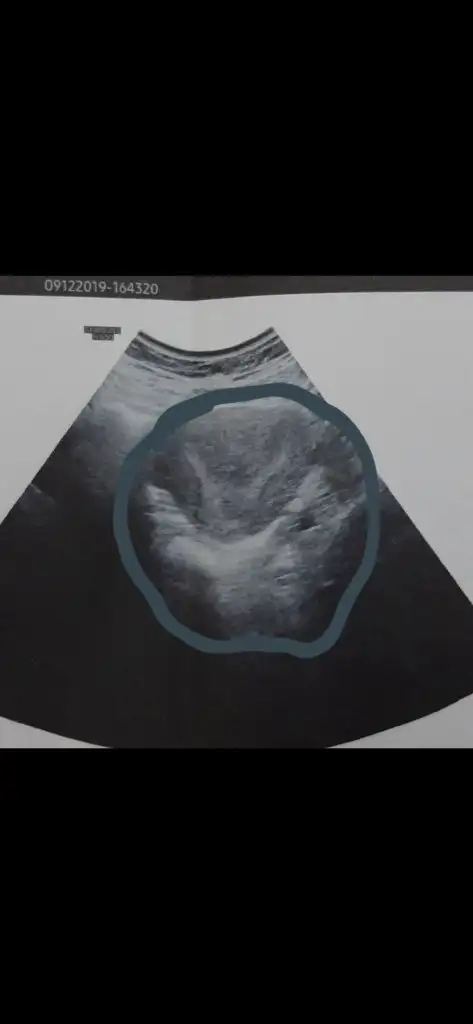

Amin canım Rabbim herkese hakkıyla annelik babalık nasip etsin inşallah. Bende önümüzdeki hafta Ankara’da Bülent zeyneloğlu nda rahim düzeltme ameliyatı olacağım. Benim hsg sonucu sağ tüpüm tıkalı sol hafif açık gibi çıktı ama Bülent hoca hsg nin çok kötü çekildiğini, histereskopi ile birlikte laparoskopi de yaparak tüplerin ne durumda olduğunu görmek istediğini söyledi. Eğer tüplerimde sorun varsa direk tüp bebeğe geçeceğiz zaten ama o süreci hiç yaşanmadan kendiliğinden olmasını çok istiyorum. Sen iki kere histereskopi olduğuna göre gayet kolay bir operasyon diye tahmin ediyorum ancak Bülent hoca benim için rahim çok aşırı y o yüzden tek operasyonla düzenlmeyebilir dedi. Umarım tek operasyonla hallolur tüplerimdede sorun yoktur hemen ertesi ay hamile kalırım. Hepsinin aynı anda olma ihtimali çok az ama Rabbim ol derse olur ne yapalım. Benim rahmim de bu şekilde bu arada

Amin canım Rabbim herkese hakkıyla annelik babalık nasip etsin inşallah. Bende önümüzdeki hafta Ankara’da Bülent zeyneloğlu nda rahim düzeltme ameliyatı olacağım. Benim hsg sonucu sağ tüpüm tıkalı sol hafif açık gibi çıktı ama Bülent hoca hsg nin çok kötü çekildiğini, histereskopi ile birlikte laparoskopi de yaparak tüplerin ne durumda olduğunu görmek istediğini söyledi. Eğer tüplerimde sorun varsa direk tüp bebeğe geçeceğiz zaten ama o süreci hiç yaşanmadan kendiliğinden olmasını çok istiyorum. Sen iki kere histereskopi olduğuna göre gayet kolay bir operasyon diye tahmin ediyorum ancak Bülent hoca benim için rahim çok aşırı y o yüzden tek operasyonla düzenlmeyebilir dedi. Umarım tek operasyonla hallolur tüplerimdede sorun yoktur hemen ertesi ay hamile kalırım. Hepsinin aynı anda olma ihtimali çok az ama Rabbim ol derse olur ne yapalım. Benim rahmim de bu şekilde bu arada.